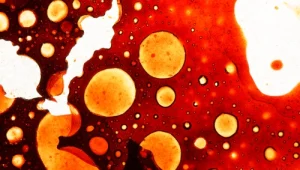

כיצד ניתן למנוע מחלות לב?

חיים בריא: כך תמנעו מחלות לב